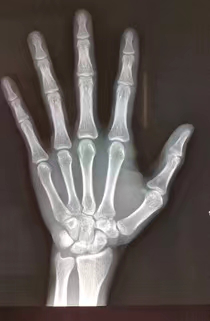

骨龄是指骨骼发育的年龄,是儿童骨骼成熟度的一种测量标准。通常通过拍摄左手腕部X光片,通过X光片观察骨化中心出现的时间、数目、形态变化及其融合时间,判断骨骼实际发育程度,来确定生物学年龄。 2.骨龄评价有何意义? 骨龄的评估,有助于了解儿童生长发育程度及性成熟的趋势,了解儿童身高发育的潜能,也可以大概预测儿童的成年身高,还可以辅助诊断某些小儿内分泌疾病。 3.骨龄如何监测及评估? 生物年龄(骨龄)-生活年龄的差值在±1岁以内的称为发育正常。 生物年龄(骨龄)-生活年龄的差值>1岁的称为发育提前(简称:早熟)。 生物年龄(骨龄)-生活年龄的差值<-1岁的称为发育落后(简称:晚熟)。 骨龄发育异常,代表孩子身体的某些方面出现了问题,而且影响了孩子身高的发育。 (性早熟的时候,骨骺提前融合,成年最终身高降低!) 4.骨龄评价有何意义? 导致骨龄提前的因素:性早熟、肾上腺皮质增生症、肿瘤、甲亢、单纯性肥胖等。 导致骨龄落后的因素:生长激素缺乏症、Turner综合征、甲减、软骨发育不全等。 身高停止生长的标志:骨骺闭合。(男童16岁,女童14岁) 骨骺未融合的骨龄图 骨骺融合的骨龄图 5.如何科学管理身高? 1. 到正规医院的儿童内分泌科就诊。 2. 骨龄测定。 3. 合理饮食,营养均衡。建议每天300~500ml的牛奶,1个鸡蛋,适量的各种肉类、谷类及水果蔬菜,同时注意科学补充维生素D。不建议吃营养滋补品,如海马、田七、燕窝、人参、蜂皇浆、牛初乳、滋补中药材等。 4. 充足的睡眠。生长激素在深度睡眠1小时左右分泌最旺盛,夜间分泌较白天多,建议最迟晚上10点前入睡。 5. 科学的运动。多进行跳绳、打篮球、羽毛球、游泳、跑步等拉伸的体育运动可促进长高。每次运动心率不超过140次/分。 6. 愉悦的心情。尽量多发掘孩子的闪光点进行夸赞,餐桌上、入睡前不打骂孩子,轻松愉快的情绪可促进生长激素分泌。 温馨提示 阳春市妇幼保健院身高管理、骨龄检查时间: 周二、周六全天 预约方式: 关注“广东省阳春市妇幼保健院”微信公众号 选择小儿内分泌专科预约挂号